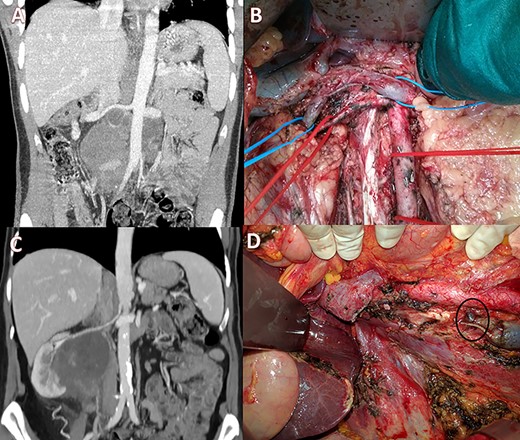

Case 1 was a 33-year-old male affected by a right testicular germ-cell tumor with enlarged retroperitoneal lymph nodes surrounding the infrarenal IVC. The patient underwent orchifunicolectomy and subsequent chemotherapy based on bleomycin, etoposide and platinum. A restaging computed tomography (CT) scan showed partial response and confirmed residual tumor involving both the IVC (with occluding thrombus) and the distal left renal vein (LRV) (Fig. 1A). CT scan also showed an efficient venous collateral pathway through the azygos−lumbar system (Fig. 1B), with no clinically evident lower limb edema. The patient underwent an en-bloc resection of the tumor mass with infrarenal IVC and LRV ligation without nephrectomy; no IVC prosthetic replacement was carried out. Recovery from surgery was uneventful with the exception of transient mild renal failure treated conservatively and without the need for dialysis. Renal ultrasonography showed regular bilateral parenchymal perfusion, and doppler ultrasonography of the lower limbs confirmed normal superficial and deep venous outflow. The patient was discharged 9 days after surgery. Histology showed a teratoma with alpha-fetoprotein expression and extensive post-chemotherapy areas of necrosis.

(A) CT scan (coronal section) of the retroperitoneal mass (asterisk) involving the IVC and LRV with congested gonadal vessels; (B) cross-section CT scan showing well-represented collateral outflow (arrow) of the renal–azygos–lumbar system.